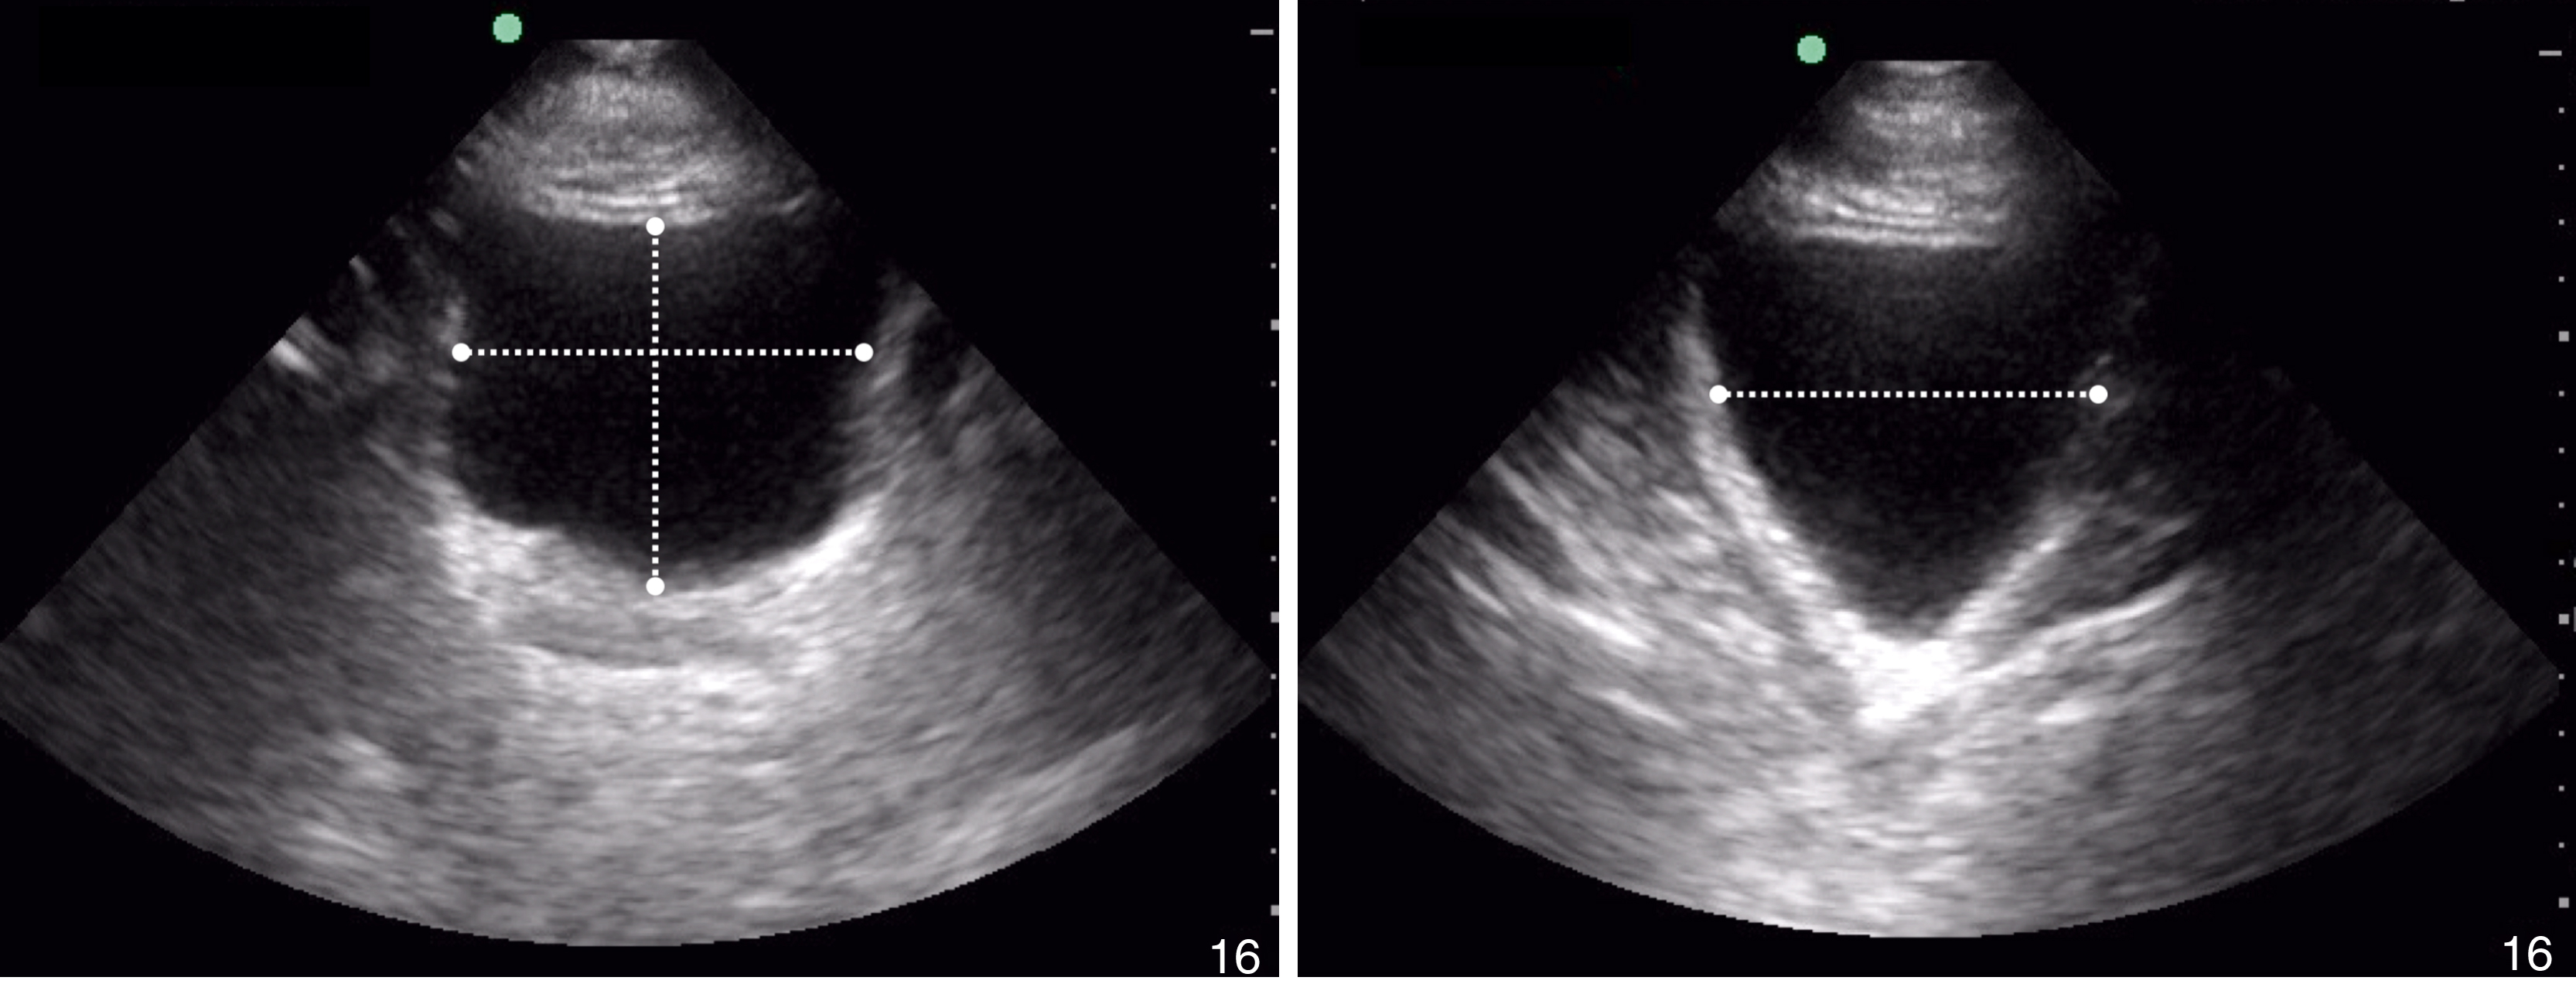

Renal US includes orthogonal views of the kidneys, with an emphasis on visualization of the renal calyces/pelvis. The sonographic windows for the two kidneys are similar to those used in the trauma upper quadrant views. The bladder view is performed from the suprapubic window in transverse and sagittal planes. Ureteral jets can be assessed by placing color Doppler over the trigone of the bladder in the transverse view. Bladder volume calculations ( Fig. e3.5 ) may be performed with on-machine calculators or by using the formula:

Bladder volume measurements.

Pericardial fluid is typically anechoic, although it can contain internal echoes in cases of pericardial hemorrhage or infection. Large pericardial effusions are usually circumferential but can be loculated. As a result, assessment for pericardial effusion should include multiple views, when feasible, to confirm diagnosis and to avoid mistaking the epicardial fat pad for a pericardial effusion. Although cardiac tamponade is a clinical diagnosis, there are several suggestive echocardiographic features, including diastolic collapse of the RV ( Video e3.9 ), loss of respiratory variation of the IVC ( Fig. e3.11 ), and transvalvular flow velocity paradoxus.

Plethoric IVC showing where to take a measurement.